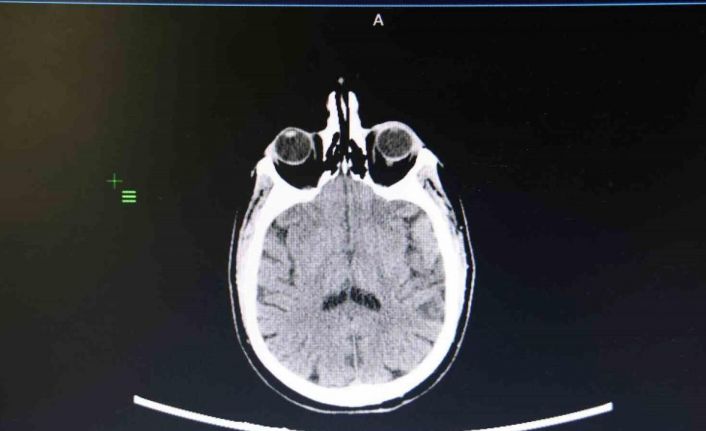

Elazığ Fethi Sekin Şehir Hastanesinde görevli Kulak Burun Boğaz (KBB) Uzmanı Prof. Dr. Öner Sakallıoğlu, işitme kaybı hakkında açıklamalarda bulunarak vatandaşlara tavsiyelerde bulundu. İşitme kaybının toplumdaki her yaşta görülebileceğini ve sıklıkla rastlanabileceğini aktaran Prof. Dr. Öner Sakallıoğlu, "İşitme kaybı her yaşta görülebildiği için bulunduğu dönem itibariyle gerek bir engel teşkil etmesi gerekse de iletişimi engellemesi ya da çocuklarda dil gelişmesi sorunlarına yol açması bakımından oldukça önem taşımaktadır. İşitme kaybı genelde hastaların işitmelerinin az olmasını ifade etmesiyle ortaya çıkar. Yeni doğan bebeklerde pek mümkün olmasa da onlarda yapılan çeşitli testlerde bu işitme kaybı ortaya çıkartılabilmektedir. Tedavi süreçleri genel olarak yaşla ilgili sebeplere bağlı olarak değişebilmektedir. Çünkü oldukça farklı sebepleri olabilir. Özellikle çocukluk çağı başta olmak üzere erişkin çağ ve daha ileri yaş olan yaşlılık döneminde çeşitli yöntemlerle tanı ve tedavisi yapılabilmektedir. Halk arasında doğru olarak bilinen fakat tıp dilinde yanlış olanların belki de en önemlisi işitme kaybının tedavisinin olmayacağı yönünde bir görüş hakim. Fakat işitme kaybının çok büyük bir kısmı tedavi edilebilmektedir. Gerek ameliyat yöntemleriyle gerekse de tedavi yöntemleriyle işitme kayıplarının çok büyük bir kısmı tedavi edilebilmektedir. Özellikle kulak çöplerinin kullanımı çok doğru olmayabilir. Toplumda çoğu insan kulağını temizlemek amacıyla kulak çöpü ya da başka cisimler kullanmaktadır. Bunların sıkıntılara yol açma ihtimalleri oldukça yüksektir. Kulak salgısının azaltılmasına yol açarak kulağın kurumasına ve kaşıntıya yol açabilir. Onun haricinde kulakta yabancı cisimler oluşturabilir. Bunlar kulak zarı yırtılmasından tutalım da kulak kanalının çizilmesi ve dış kulak enfeksiyonlarının ortaya çıkması gibi sorunlara neden olabilir. Bunların tedavisi mümkün fakat kulak çöpü gibi yabancı cisimlerin kullanılmasını çok tavsiye etmemekteyim. Çoğu vatandaşta dış kulak kanalından sarımsı bir şekilde gelen sıvı akıntısı olmaktadır. Bunlar kulağımızın normal bir salgısıdır. Bunların illa temizlenmesi gerekmiyor. Daha önce bahsettiğimiz gibi bunların fazlaca temizlenmesi dış kulak kanalında travmalara belki de istemediğimiz enfeksiyonlara yol açabilmektedir. Bu yüzden sakıncası bulunmaktadır" dedi.